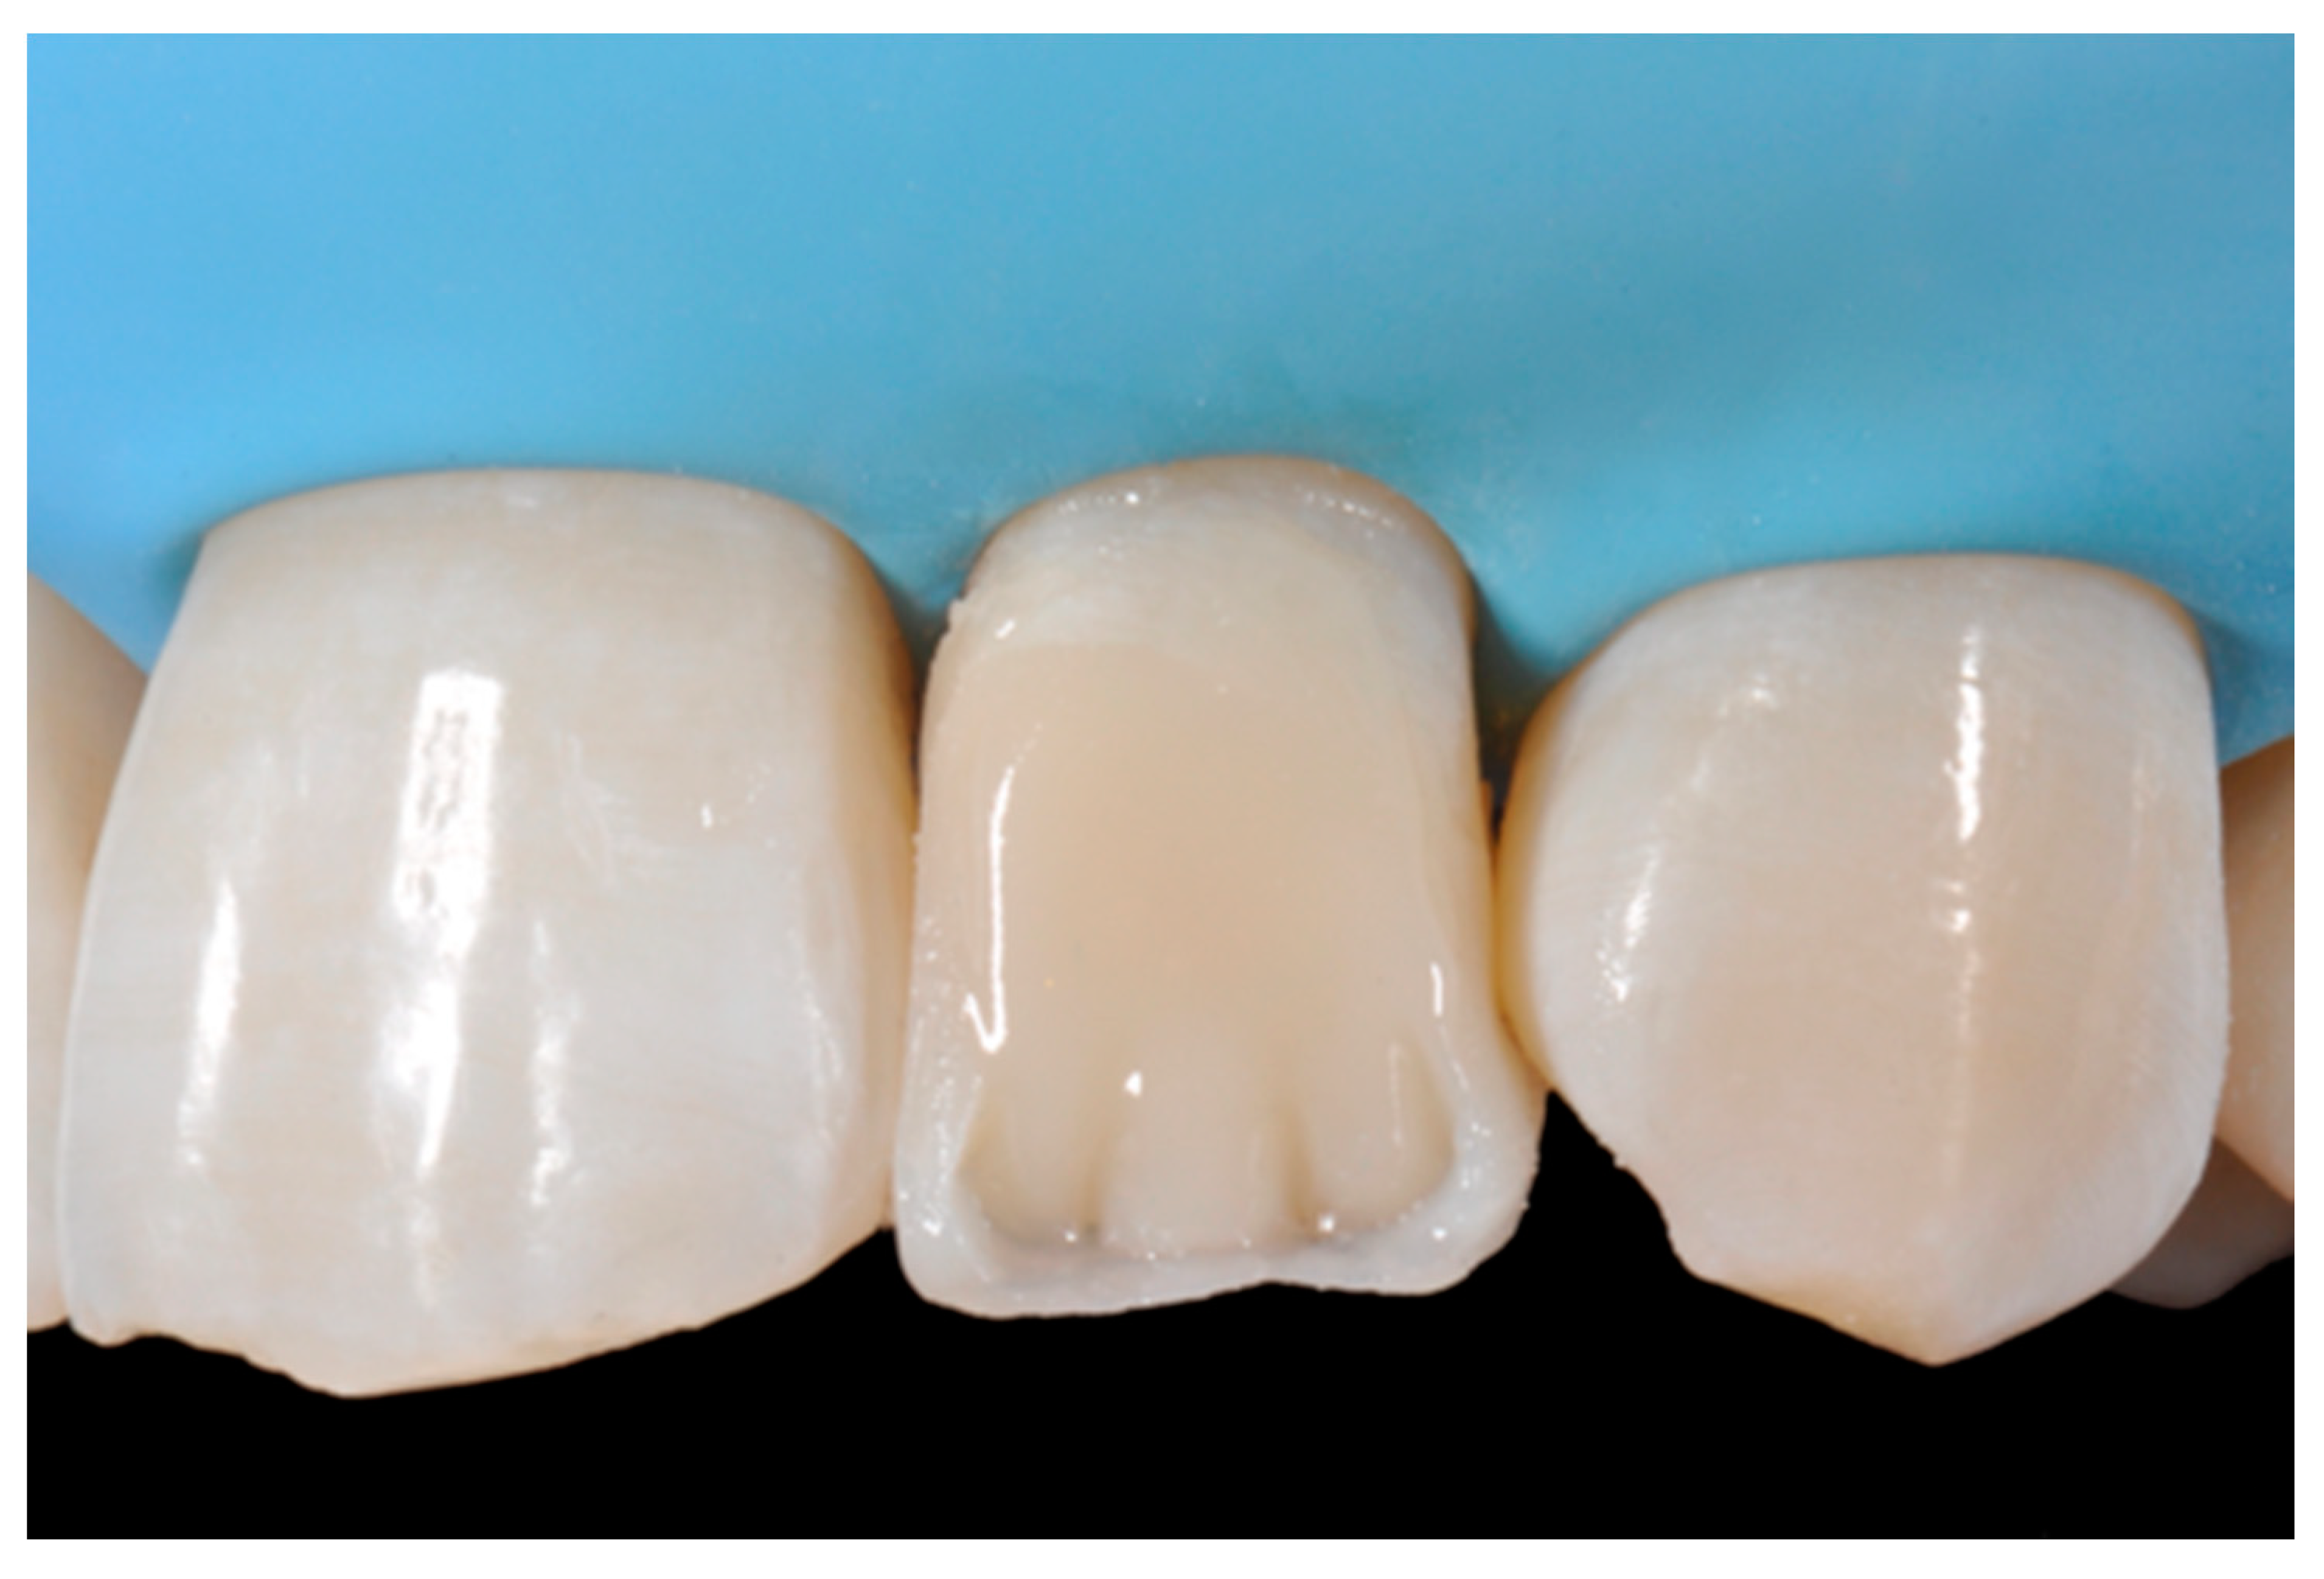

Figure 12.

Enamel layer applied. Reprinted from Restauri diretti nei settori anteriori, G. Paolone, S. Scolavino, © 2021, with permission from Quintessence Publishing Italy.

Finishing and polishing procedures were performed with a diamond bur (WL 268 014 Horico, Berlin, Germany), silicone points (Identoflex, Kerr, Bioggio, Switzerland) brushes (Jiffy Goat Air Brushes, Ultradent Products, South Jordan, UT, USA), and diamond pastes (Diamond Polish Mint, Ultradent Products, South Jordan, UT, USA) (Figure 13 and Figure 14). Satisfactory clinical and radiographic outcome was considered satisfactory at 3-months, 1-year, and 5-years post-operative (Figure 15, Figure 16, Figure 17, Figure 18 and Figure 19).